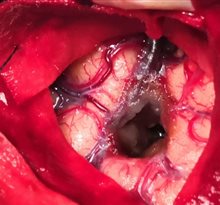

小骨窗开颅脑内血肿清除术

小骨瓣                               清除血肿